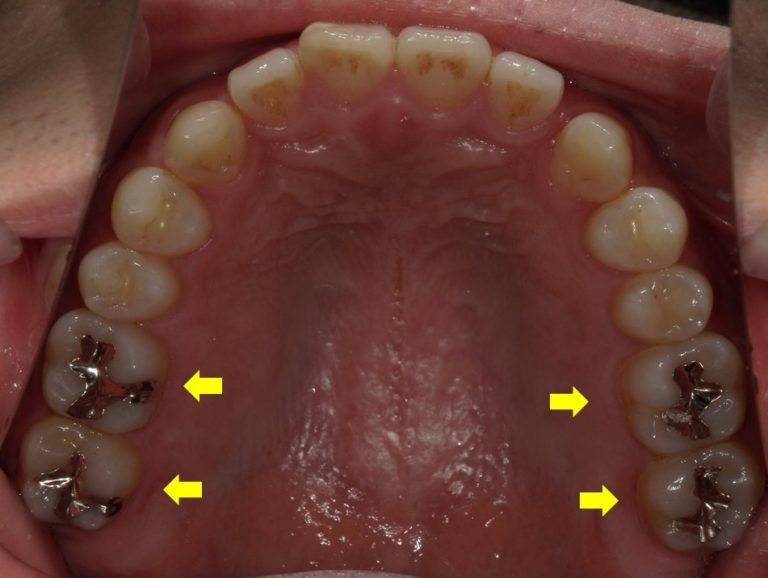

一部条件はありますが、いわゆる4番、5番、6番の歯については白い被せ物も可能となってきました。

また被せ物以外の詰め物については、当院では隣接面といって歯と歯の間まで虫歯になっていない場合ではあれば、積極的に保険の白い詰め物(コンポジットレジン)で修復するようにしています。

(隣接面のコンポジットレジン修復は当院では状況によって行いますが、選択できない場合もあります。それは技術的な難しさや予後のことを考えての判断です。)